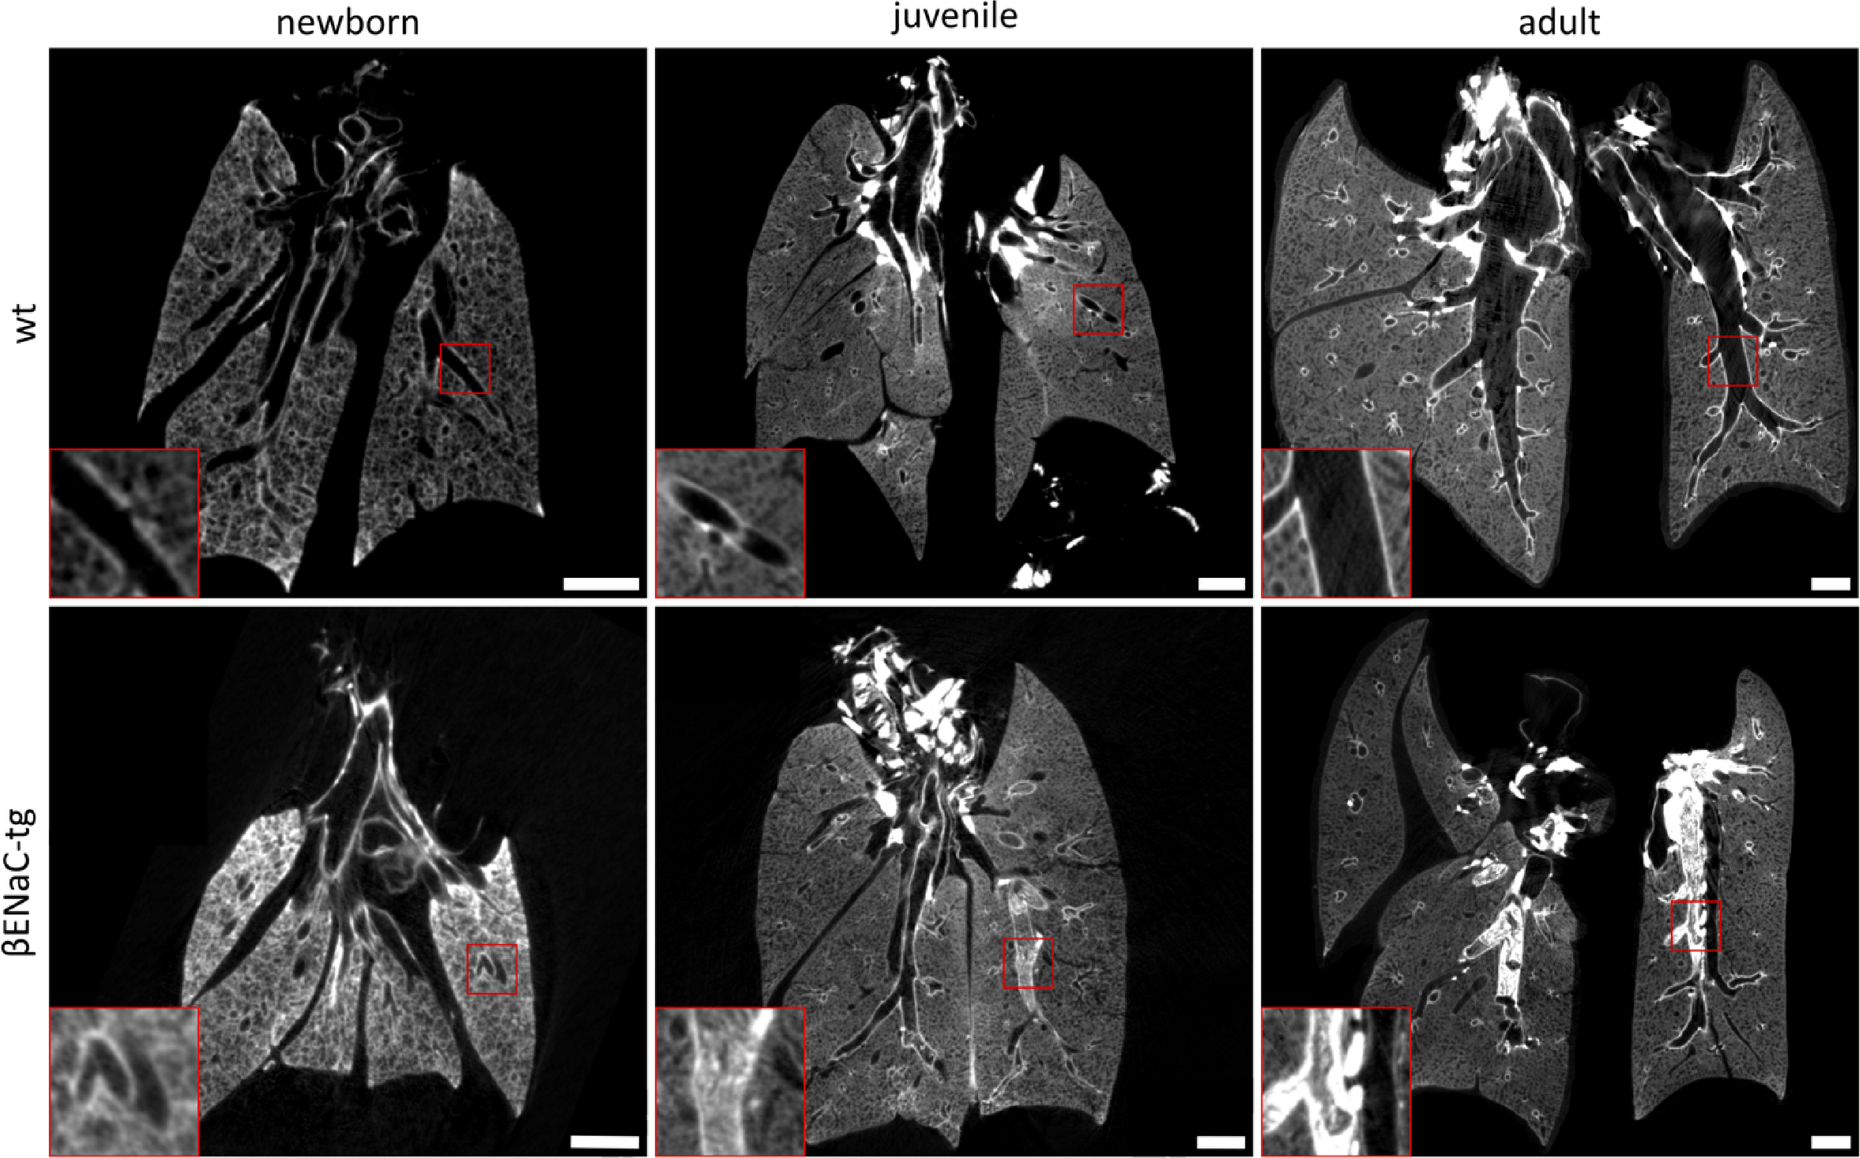

Fig. 2

µCT imaging revealed age-dependent progression of airway mucus obstruction in βENaC-tg mice. Representative µCT reconstructions illustrating the age-dependent progression of airway mucus obstruction in βENaC-tg mice, compared to wild-type. Images show newborn, juvenile, and adult stages for both genotypes. Note the spontaneous formation and accumulation of mucus plugs in βENaC-tg mice from juvenile to adult stages, which is absent in wild-type mice. Red boxes mark regions magnified 3x. Scale bars are 1 mm. µCT = micro-computed tomography. wt = wild-type. βENaC-tg = βENaC-transgenic.